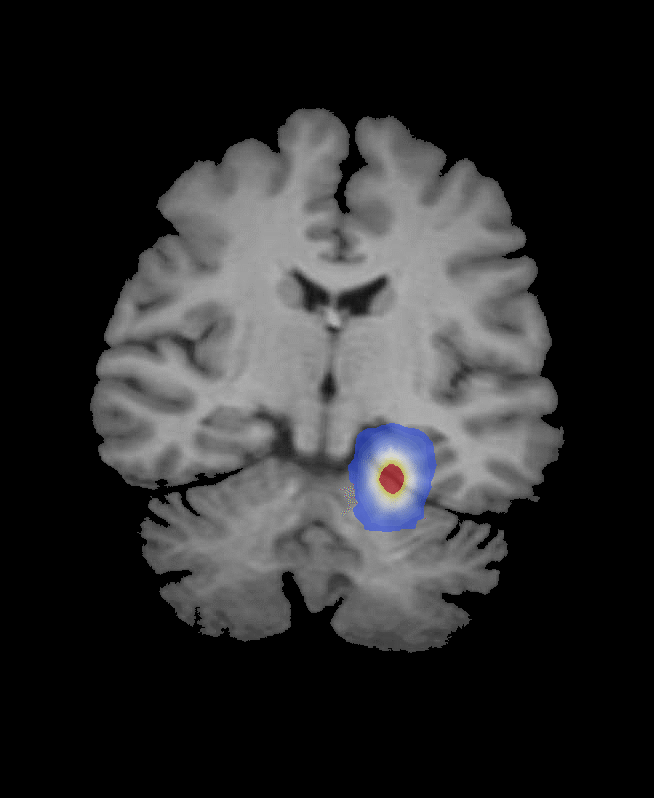

frames = Table[ImageCompose[img, {ContourPlot[sols[i, 1 - x, y], {y, 0, 1}, {x, 0, 1}, PlotRange -> {{0, 1}, {0, 1}, {0.01, All}}, PlotPoints -> 1, Contours -> 20, ContourLines -> False, AspectRatio -> 798./654., ColorFunction -> "Temperature", Frame -> False], 0.6}], {i, 0, 200, 20}];

![ListAnimate[frames]](/c/portal/getImageAttachment?filename=frames.gif&userId=557417)